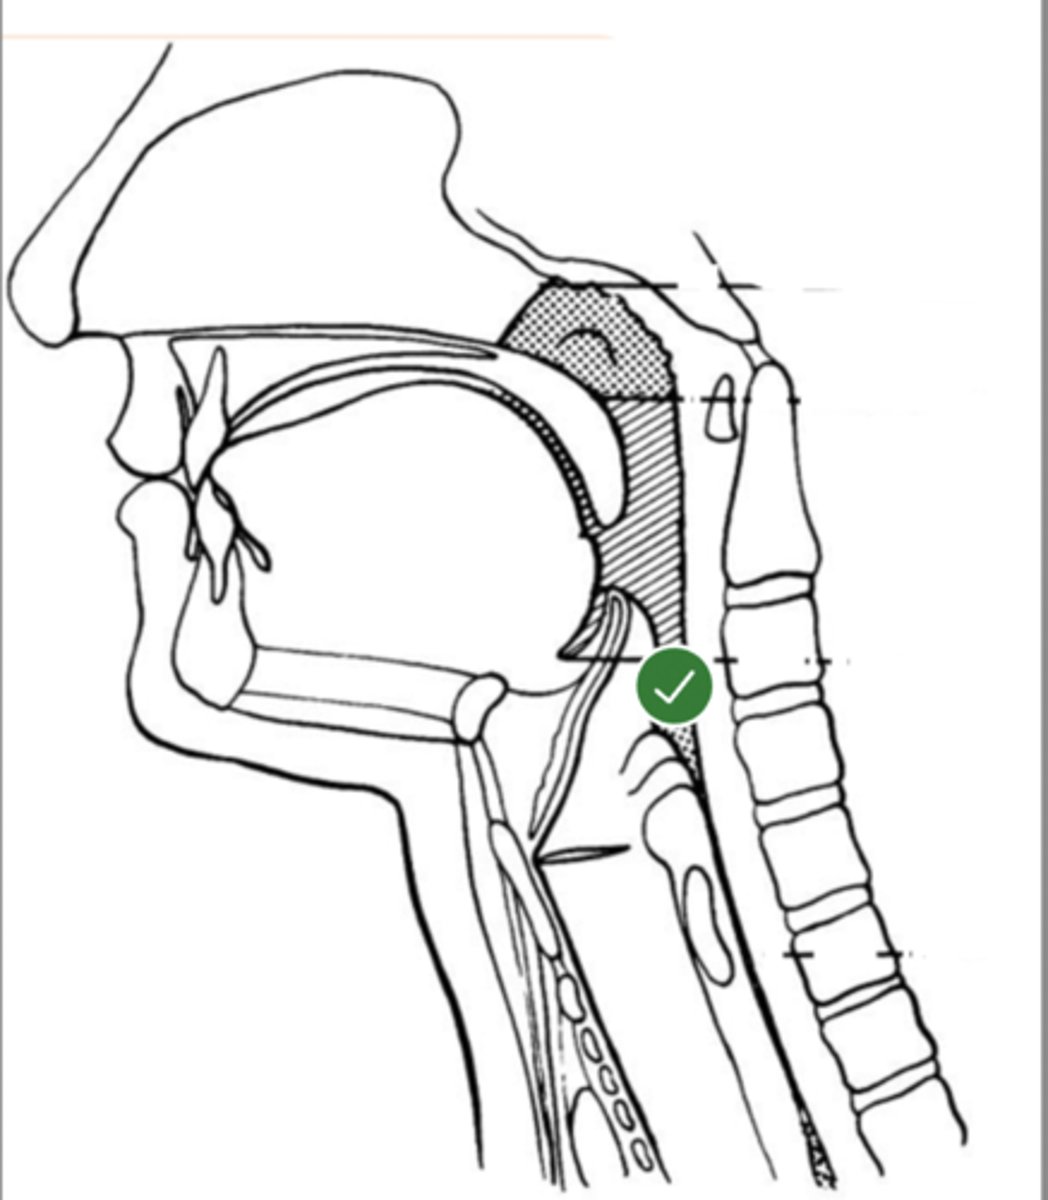

Label hypopharynx/ hylolarynx

label Line of true vocal folds (lateral view)

label Thyroid cartilage (anteriorly) (lateral view)

Label posterior cricoid (lateral view)

Label esophagus (lateral view)

Label base of tongue (lateral view)

label anterior tongue (lateral view)

Label posterior/ back of tongue (lateral view)

Label Mandible (lateral view)

Label velum/ soft palate (lateral view)

Label hyoid bone (lateral view)

Label epiglottis (lateral view)

Label thyroid cartilage (lateral view)

Label trachea (lateral view)

Label upper esophageal sphincter (lateral view)

Label posterior pharyngeal wall (lateral view)